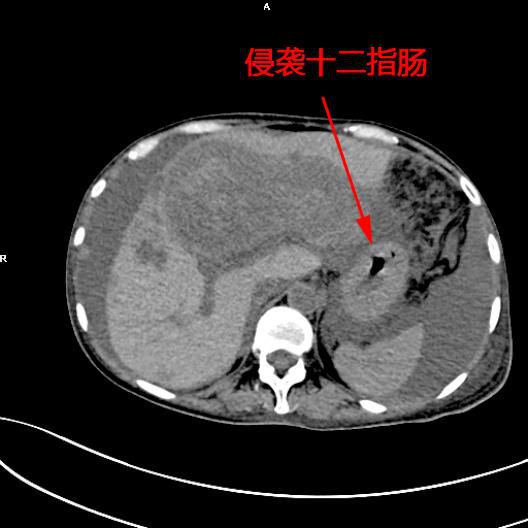

患者陳女士,57歲,汕頭潮南人,2個月前出現右上腹痛,在汕頭大型三甲醫院确診爲膽囊癌,因腫瘤爲晚期,已擴散至肝髒、十二指腸,患者放棄在汕頭治療,回家後自行采用中藥治療。近期右上腹痛加重,反複排黑便,遂來我院住院,診斷爲膽囊癌伴活動性出血。

5月11日下午,内三科主任李旭丹、影像科副主任胡志華上台施術。通過粵東領先的飛利浦DSA造影顯示,患者腫瘤供血血管豐富,膽囊動脈造影可見腫瘤染色明顯,有造影劑外溢,提示部分血管末梢有破裂出血現象,探查胃十二指腸動脈及腸系膜上動脈未見出血征像,豐富的血供使腫瘤能獲取大量的營養快速生長,血管末梢的破裂出血導緻患者反複黑便。